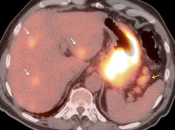

• The utility of PET/CT lies in its assessment of regional nodes and distant metastatic disease.

• Distant Disease: Most commonly to the liver, peritoneum, lung and bone.

• Obviously, signs of associated metastatic disease on the scan give the radiologist much greater confidence in reporting a suspected primary gastric lesion.